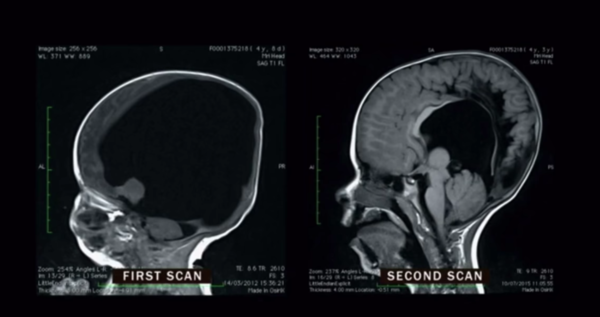

Doktorlar Beyni Olusmadigindan Anneye Bebegi Almayi Onerdi 4 Yil Sonra Ise Doktorlar Sok Oldu